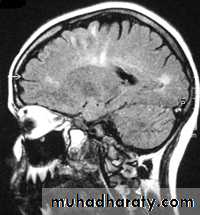

Sagital section of brain ( T1 w post contrast injection)

Sagittal fluid-attenuated inversion recovery (FLAIR) weighted image through a brain lesion), showing homogeneity of the lesion, lack of a perceptible wall, lack of internal complexity, and CSF signal intensity. There is associated brain displacement. These imaging features are typical of an arachnoid cyst.